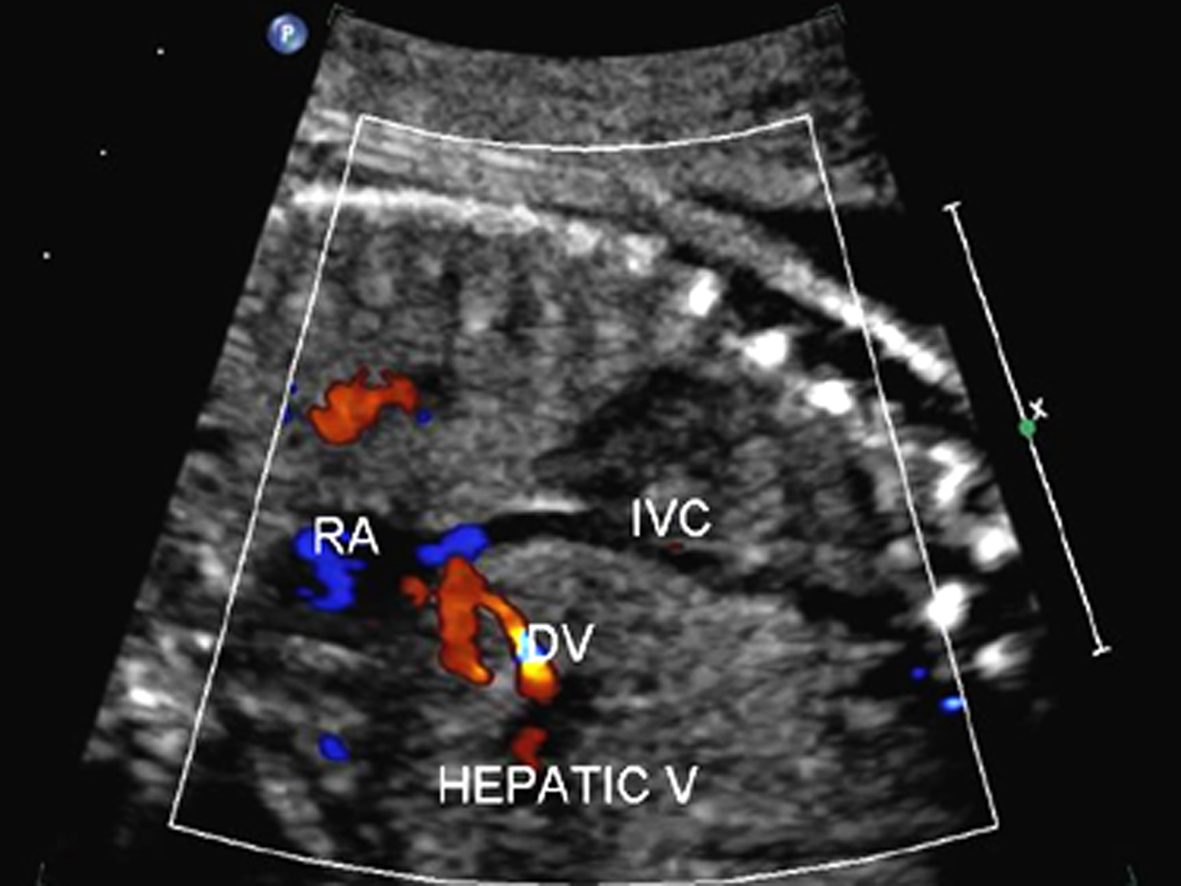

2.检查内容 观察彩色多普勒显示的过房室瓣、半月瓣、卵圆孔瓣的血流及各血管内(包括上下腔静脉、肺静脉、主动脉、肺动脉、主动脉弓、动脉导管弓、静脉导管等)的血流方向是否正常,有无反向血流或五彩缤纷、色泽镶嵌的高速血流信号显示。用脉冲多普勒测量过房室瓣、半月瓣血流、测量静脉导管内血流,以了解胎儿心脏节律情况、分析心房舒缩与心室舒缩之间的关系、了解胎儿的心功能等。正常胎儿房室瓣多普勒血流时间流速曲线呈双峰频谱,E峰小于A峰(图1);有时,三尖瓣血流可表现为单峰见切迹。半月瓣血流均呈单峰,多普勒时间流速曲线图显示肺动脉瓣血流收缩期射血时间大于主动脉瓣,峰值上升支亦快于主动脉(图2)。静脉导管为连接脐静脉和下腔静脉间的一段很短的血管,直径约为1~2mm,应用彩色多普勒可发现脐静脉血流至此处时,流速增快,呈花色血流信号(图3)。正常胎儿静脉导管的血流频谱呈连续单向双期双峰血流频谱, 有两个波峰两个波谷,第一个波峰“S”峰(房室瓣的关闭下移导致心房压的下降),第二个波谷“V”谷(心室等容舒张房室瓣上移导致暂时的心房压上升),第三个波峰“D”峰(为心室舒张房室瓣开放,血流快速流入心室导致心房压下降),第四个波谷“A”谷(心房收缩)(图4)。

图3静脉导管(DV)的彩色多普勒血流图